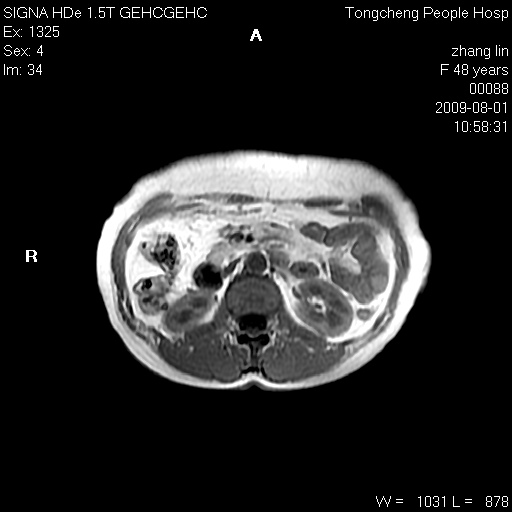

女,48岁。健康体检,彩超发现右肾占位性病变。平素健康。

临床诊断:右肾占位性病变,性质待定(囊肿?肿瘤?)。

上中腹部mr平扫+增强扫描,图像如下:

右肾上极见一类圆形病灶,t1wi呈等信号t2wi呈等高混杂信号,三期增强无强化,边界清---考虑囊肿出血。

同反相位均表现为等信号,病变无强化,考虑含蛋白的囊肿可能,弥散加权相或许有些帮助,

慢性胆囊炎